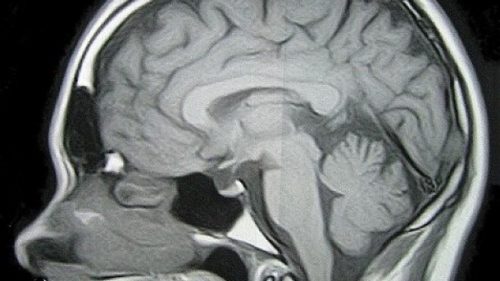

4. Penyusutan Jaringan Cortex Otak

Waspada dengan jaringan Cortex via Heal Naturally

Yap kamu tidak salah baca Cakap People. Terlalu lama menatap layar PC atau gadget, lama kelamaan akan membuat jaringan cortex di otak menjadi menipis. Sekilas penipisan ini tidak terlalu membahayakan.

Namun justru sebaliknya. Penipisan ini akan berdampak pada ketidakstabilan emosi, kegagalan dalam memproses hal-hal yang baru, dan bahkan depresi berat.